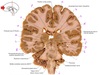

1

Q

a

body of corpus callosum

2

b

Anterior horn of lateral ventricle

3

c

Septum pellucidum

4

d

Rostrum of corpus callosum

5

e

Head of caudate nucleus

6

f

Anterior limb of internal capsule

7

g

Putamen

8

h

Nucleus accumbens